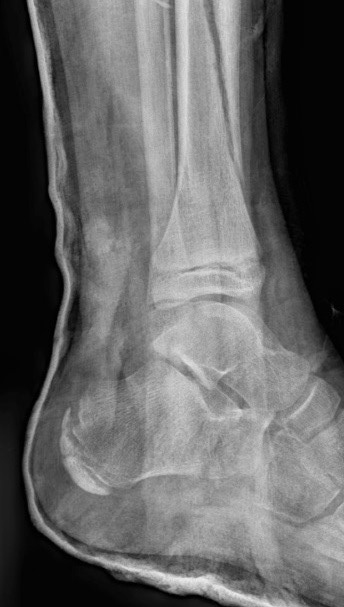

Загальна рентгенографія